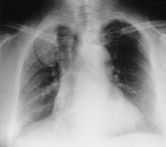

En la Rx PA de tórax(fig. 1) se observa: ausencia radiológica de mama derecha,insuflación del arco anterior y medio de la primera costilladerecha e imágenes similares de menor tamaño en elarco medio de la segunda costilla y arco posterior de laséptima. Afectación del lado derecho del manubrioesternal. En la TAC toraco-abdominal (fig. 2) se aprecia:asimetría de partes blandas, insuflación de laprimera costilla con esclerosis de la cortical ytrabeculación interior moderada, también se objetivaalteración de características similares en manubrioesternal.

Figura1.